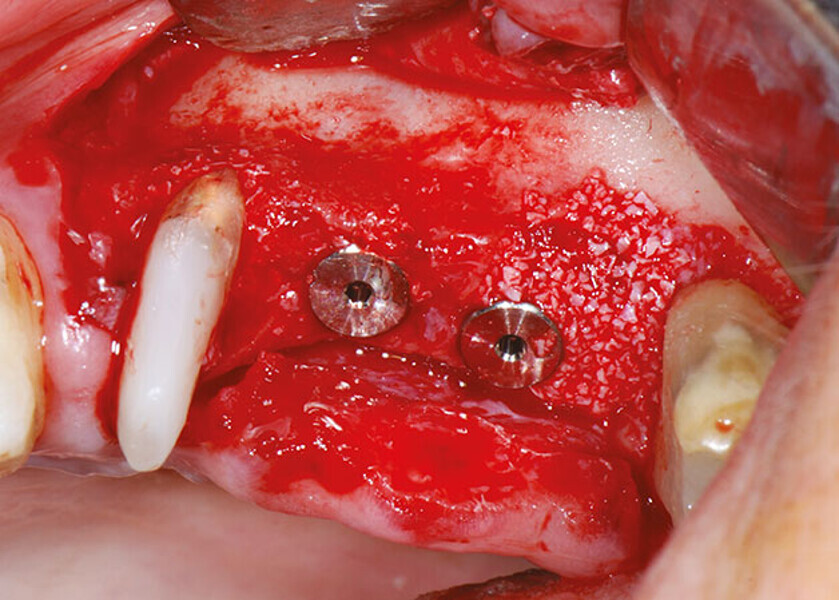

Case report